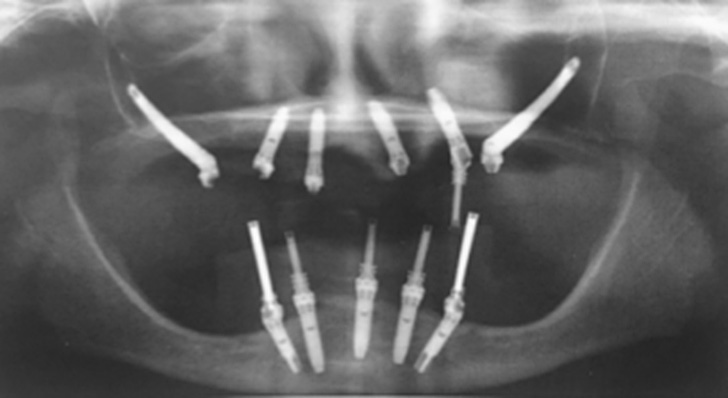

Yes, zygomatic implants are different from standart. They are longer than and have an inclination that can range from 0 ° to 60 °.

Therefore, computed tomography and orthopantomography are required, which can allow us to assess the position of your anatomical structures. The case will then be examined and a decision will be made on which method to choose.